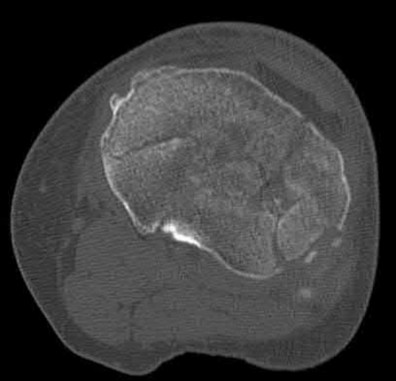

Figure 28 is the lateral radiograph of a patient who sustained an intra-articular fracture of the calcaneus. The structure (*) depicted by the arrows most likely represents which osseous component of the calcaneus?

Fractures of the calcaneus occur as a result of shear and compression forces. Foot position at the time of impact, the force of the impact, and bone quality all dictate the degree of comminution and fracture line orientation. Two primary fracture lines are consistently observed, one of which divides the calcaneus into medial and lateral portions. An essential feature of this fracture

line is that it creates a fragment (sustentaculum tali) that remains attached to the talus by the interosseous ligament. This medial portion (constant fragment) of the posterior facet retains its normal anatomic position beneath the posterior talus. Its corresponding lateral component (labeled with an * in the figure), however, can be found displaced inferiorly within the body of the calcaneus. It is often rotated 90 degrees (as depicted in Figure 28) in relation to the remainder of the subtalar joint. This gives the appearance of what has been described as the "double-density" sign. The middle facet is more anterior and less commonly displaced. The lateral wall is nonarticular.